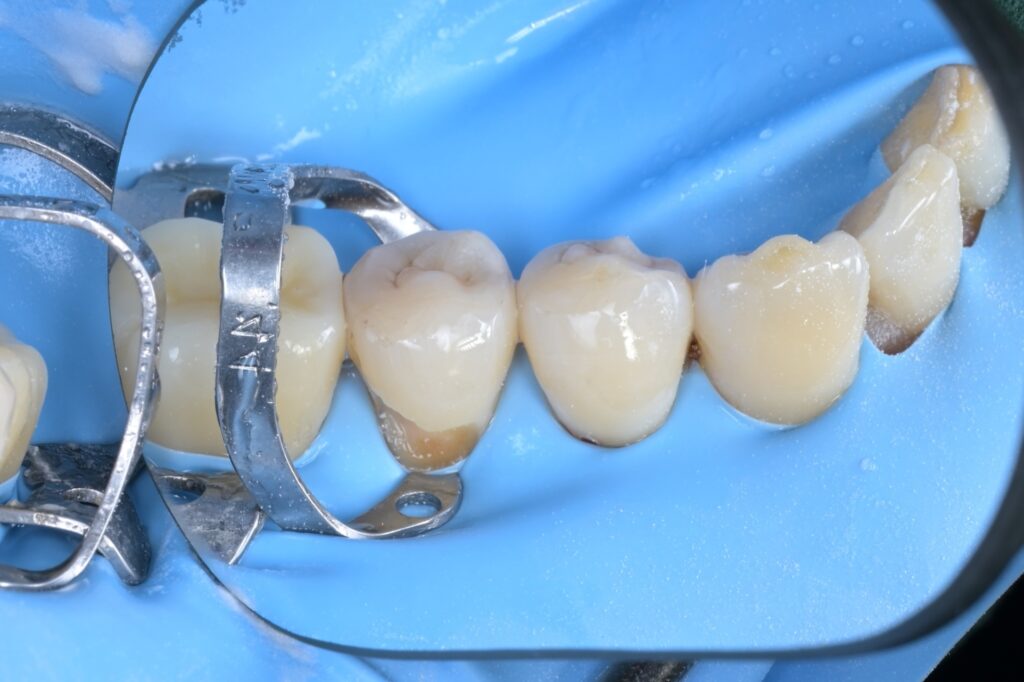

모든 과정을 마치고 러버댐과 클램프를 제거한 직후의 모습입니다.

잇몸 라인을 따라 자연스럽게 치료된 모습, 보이시나요? 잇몸이 살짝 눌려있지만, 이는 하루 이틀이면 금방 가라앉습니다. 중요한 것은 치아와 레진 사이에 틈이 전혀 없다는 점입니다.